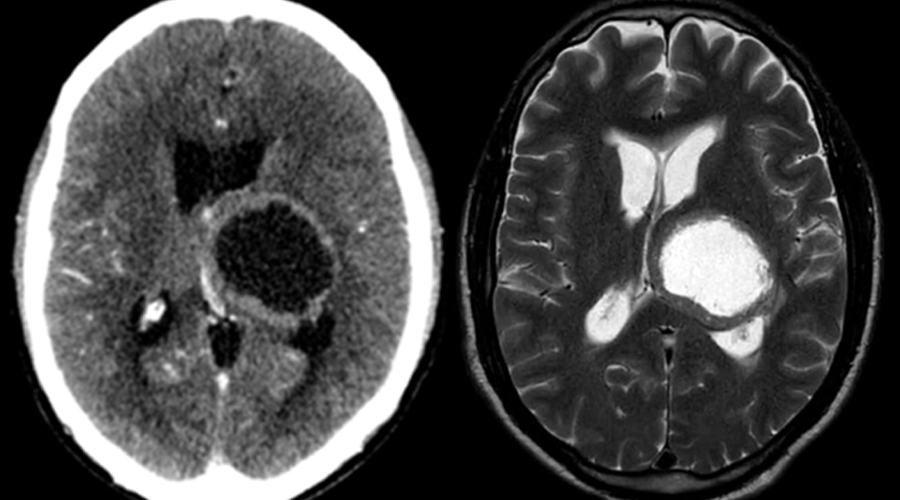

Caso 1 | Abril 2026 | Roentgen

Motivo de consulta: Convulsiones tónico clónicas generalizadas.